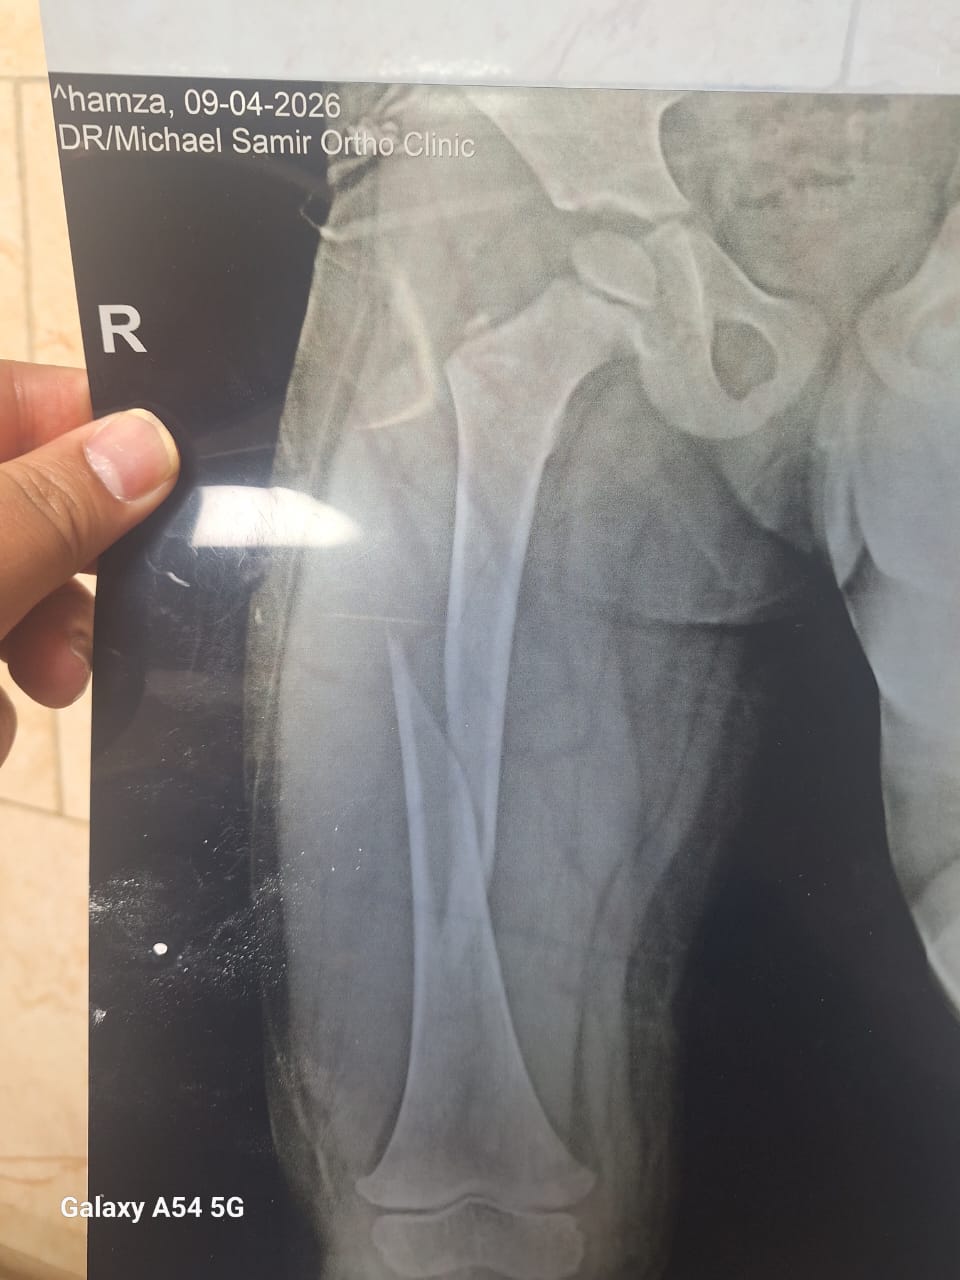

وأضاف مدير المستشفي، أنه تم إجراء 3 عمليات بقسم الأنف والأذن، و3 عمليات بقسم العظام، بالإضافة إلى 4 عمليات جراحية متنوعة، بما يعكس جاهزية الأقسام المختلفة بالمستشفى لتقديم خدمات طبية متكاملة للمرضى